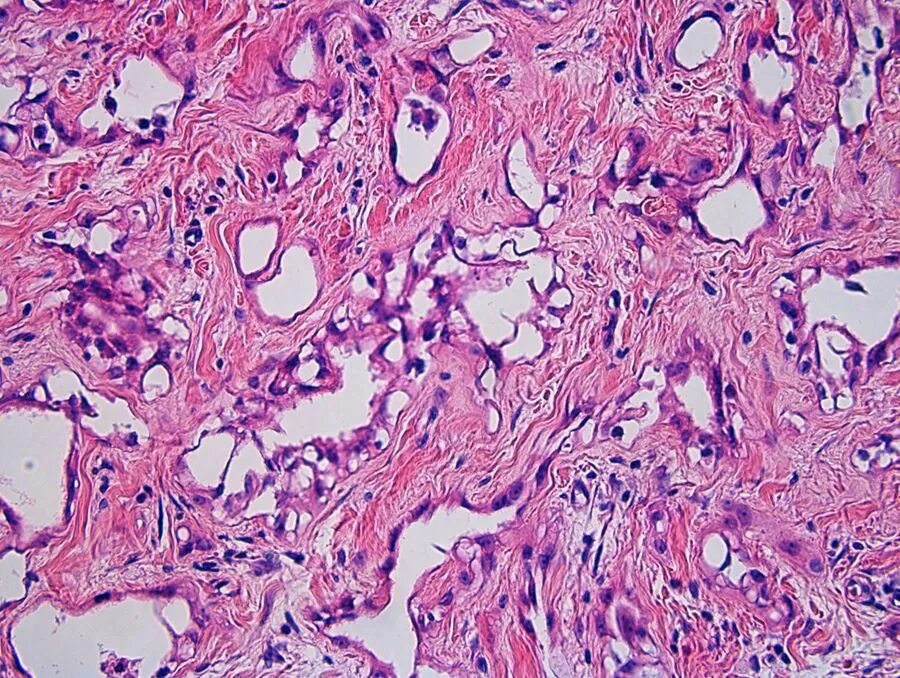

Молекулярная гистология